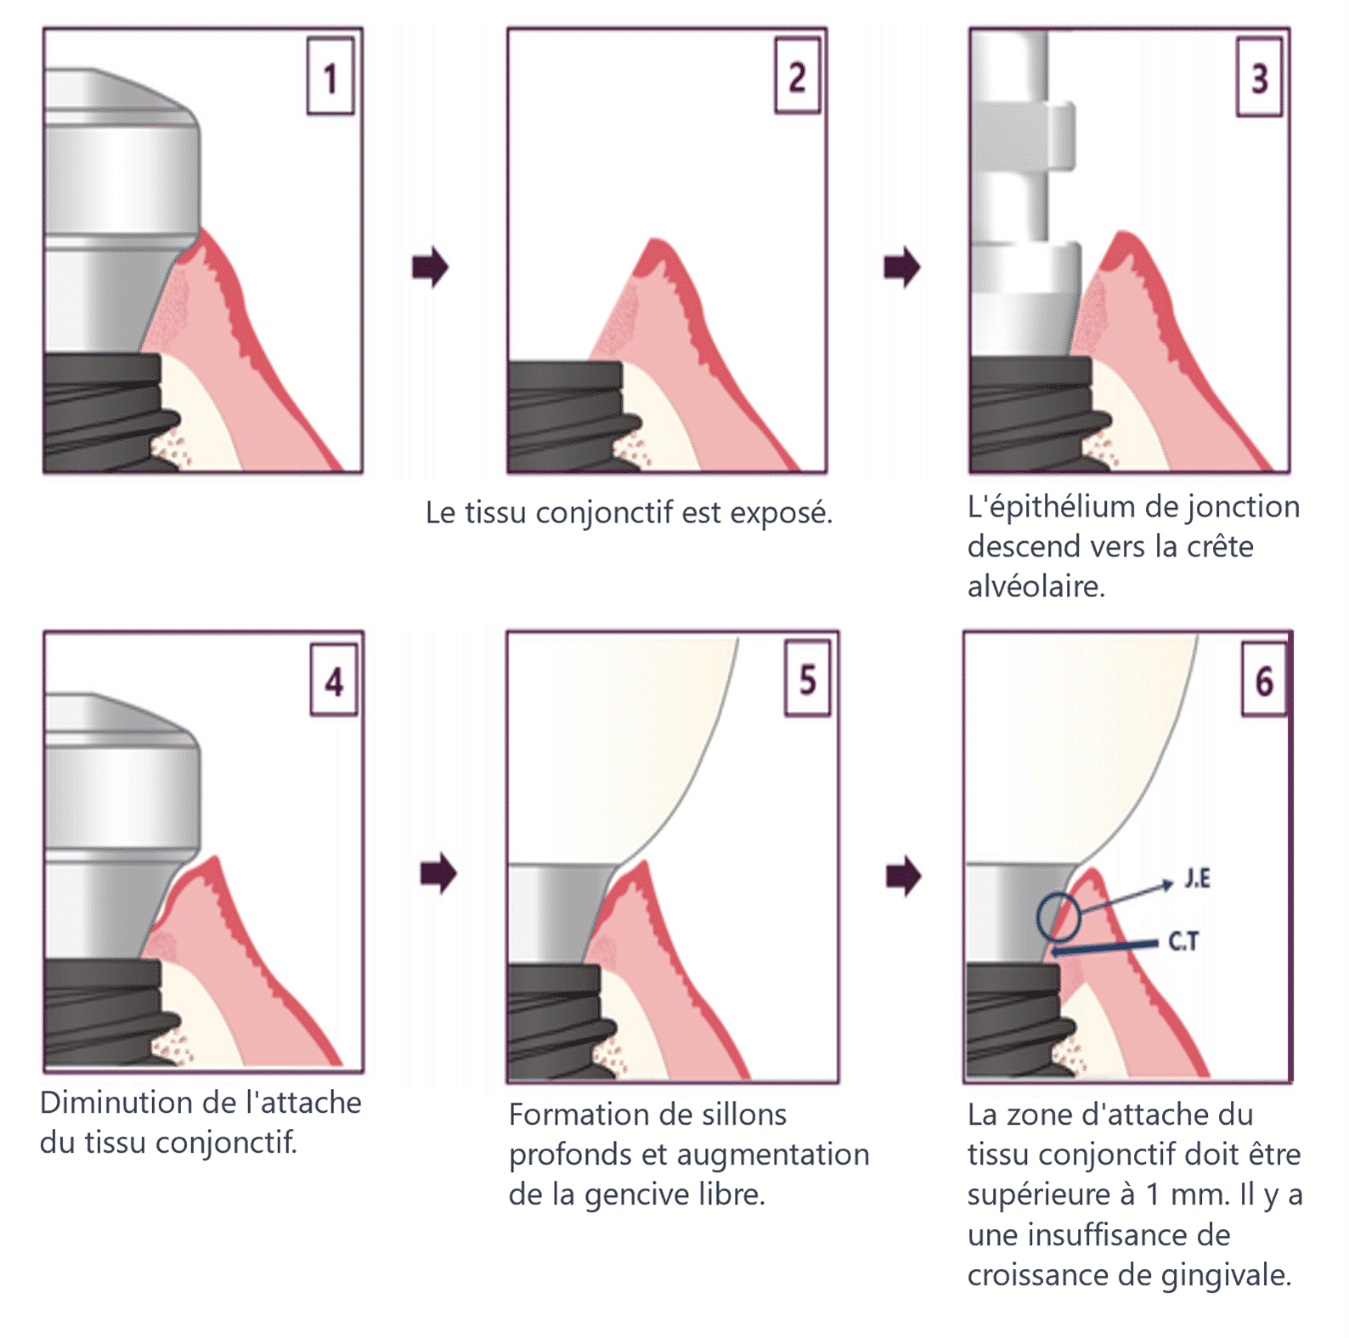

(Figure 4) Processus de prise d’empreinte et de mise en place de la couronne des implants bone level, en deux parties.

La figure 4 illustre le processus de prise d’empreinte et de mise en place de la couronne pour les implants bone level en deux parties.

Comme le montre le diagramme, lors de la série de processus associés à la prise d’empreinte et à la pose de la couronne avec les implants bone level en deux parties, il est possible que le tissu conjonctif attaché au pilier se détache, ce qui peut entraîner une perte d’os crestal au niveau de l’os alvéolaire.